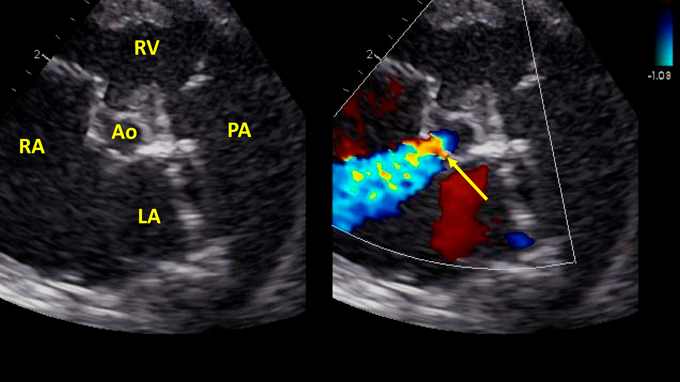

Pediatric Cardiology and Cardiac Surgery 36(4): 328-333 (2020)

Fig. 4 Short axis view reveals continuous flow shunting from aortic root to RA (arrow). See Movie B

Ao, aorta; LV, left ventricle; RA, right atrium; RV, right ventricle, PA, pulmonary artery

胎児心エコー所見と同様,心室中隔欠損を合併した非典型的左心低形成症候群(僧房弁閉鎖,大動脈弁閉鎖)と診断した(Fig. 3).上行大動脈径は5 mmで,上行大動脈の血流は動脈管を介して逆行性に維持されていた.卵円孔は2 mm大で開存していたが狭小であり,左右短絡の通過血流速度は2.0 m/sであった.しかし,胎児心エコー検査でみられた中等度の三尖弁逆流は認めず,大動脈基部から右房へ短絡する連続性の血流を認めた(Fig. 4, Movie B).右室の収縮能は良好であった.